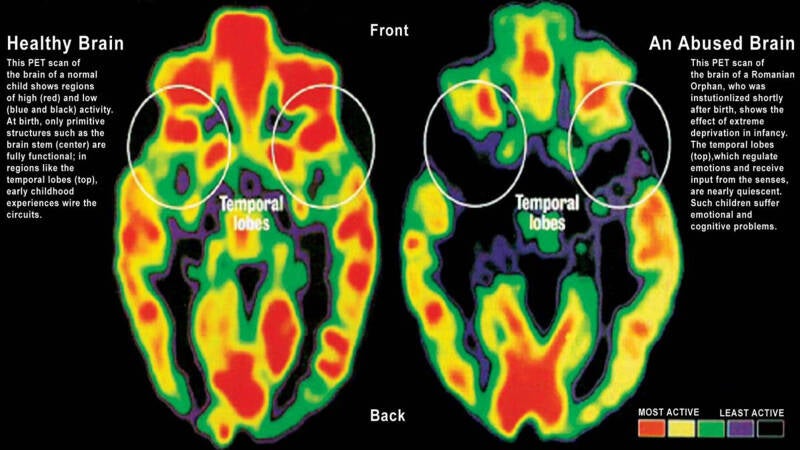

TEP and PET scan = Same TEP (Tomographie par Émission de Positons) is the French term for PET (Positron Emission Tomography) scan